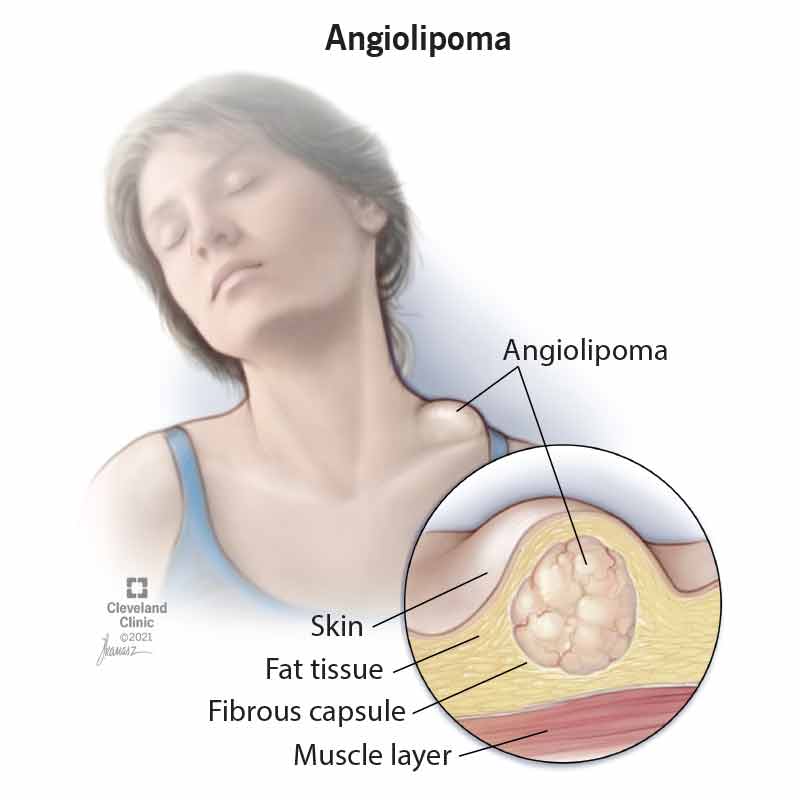

Angiolipoma: Symptoms, Causes and Treatment